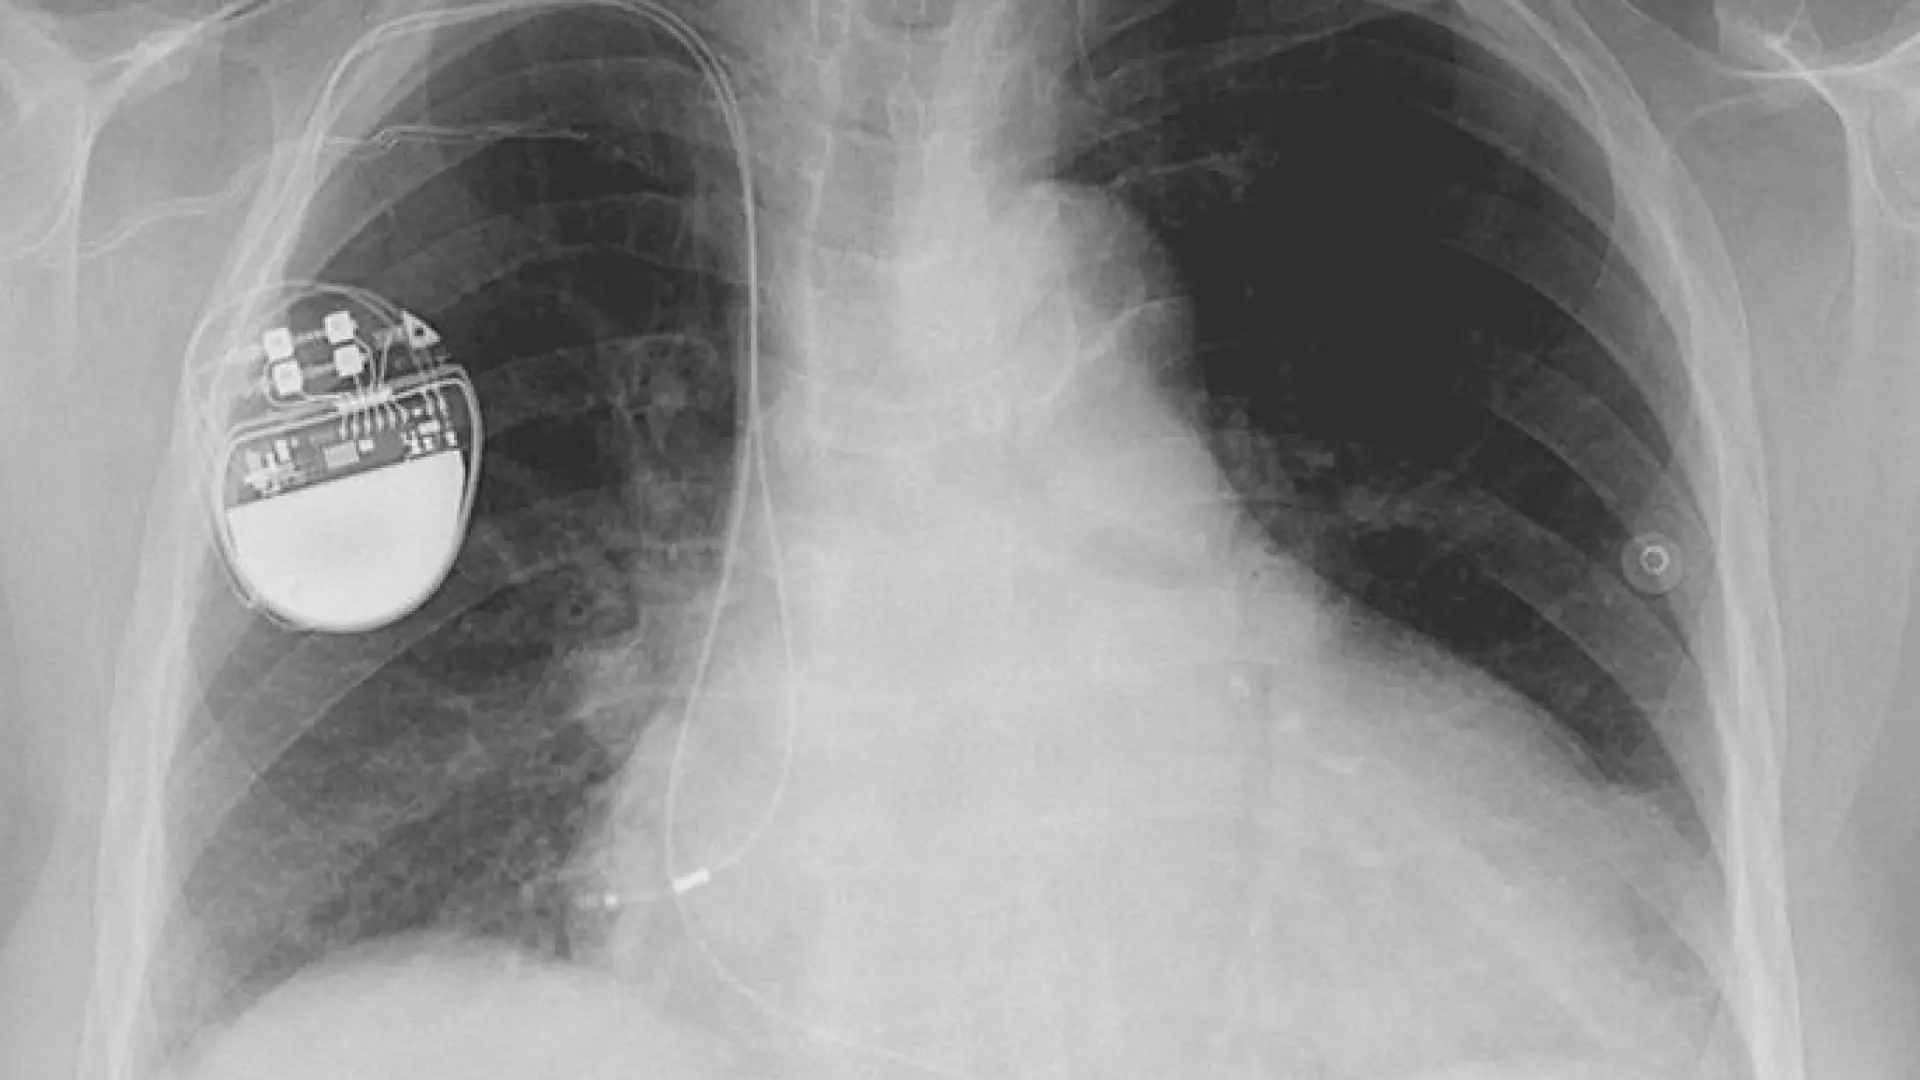

Inquietud entre las personas con marcapasos por el riesgo de los imanes de las balizas V-16: "¿Y qué hago, si normalmente conduzco sola?"